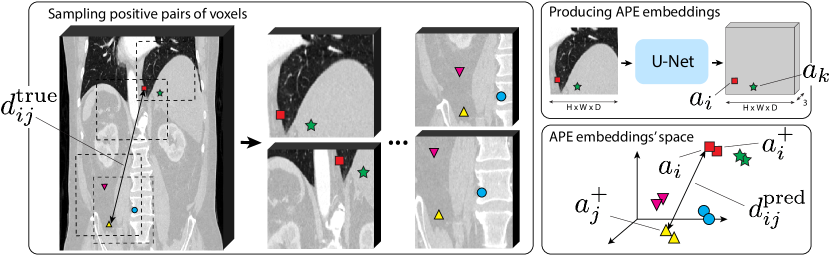

Figure 1: Illustration of APE training procedure. Left: sampling n𝑛n pairs of overlapping augmented patches and N𝑁N positive pairs of voxels from the overlapping regions, denoted by the markers of the same color and shape. Top-right: predicting the APE map for each patch and extracting the APE embedding for each sampled voxel. Bottom-right: the relative positions of the positive pairs of voxels in the APE embeddings’ space. We train APE such that distances dijpredsuperscriptsubscript𝑑𝑖𝑗predd_{ij}^{\text{pred}} between the APE embeddings are similar to the distances dijtruesuperscriptsubscript𝑑𝑖𝑗trued_{ij}^{\text{true}} between the voxels’ normalized absolute positions in the 3D physical space.

The core idea of APE is to learn how radiological features are located w.r.t. each other in the 3D physical space in an “average patient”. We implement this idea by sampling different voxels from the same volumetric image and training APE to embed them in a 3D positional embeddings’ space based on their local appearances. The main training objective is to make the distances between predicted positional embeddings highly correlated with the physical distances between the corresponding voxels. Although physical distances are defined only between voxels from the same volume, APE embeddings of similar anatomical landmarks in different patients occurs well-aligned with each other. Therefore, it is natural to call them anatomical positional embeddings.

Below, we detail the APE architecture and its training procedure, illustrated in Figure 1.

In order to achieve the expected local properties of the APE embeddings, such as better alignment with the anatomical landmarks at local scale and equivariance w.r.t. different image crops, changes of its voxel spacing, and color distortions, we propose the following improved training procedure. Inspired by contrastive learning of voxel-level representations [9, 3], we sample n𝑛n pairs of overlapping augmented patches and sample N=nk𝑁𝑛𝑘N=n\cdot k positive pairs of voxels from their overlapping regions, i.e., pairs of voxels from different patches but having the same absolute positions {pi}i=1Nsuperscriptsubscriptsubscript𝑝𝑖𝑖1𝑁\{p_{i}\}_{i=1}^{N} in the original image; see Figure 1. Patch augmentations include rescaling to random spacing, random masking, random gaussian blur/sharpening/noising, and clipping the intensities to random Hounsfield window. Then, we predict the APE embeddings {(ai,ai+)}i=1Nsuperscriptsubscriptsubscript𝑎𝑖superscriptsubscript𝑎𝑖𝑖1𝑁\{(a_{i},a_{i}^{+})\}_{i=1}^{N} for all the N𝑁N positive pairs of voxels and compute the pairwise distances dijpred=aiaj+2subscriptsuperscript𝑑pred𝑖𝑗subscriptnormsubscript𝑎𝑖superscriptsubscript𝑎𝑗2d^{\text{pred}}_{ij}=\|a_{i}-a_{j}^{+}\|_{2}. The target distances dijtrue=p^ip^j2subscriptsuperscript𝑑true𝑖𝑗subscriptnormsubscript^𝑝𝑖subscript^𝑝𝑗2d^{\text{true}}_{ij}=\|\hat{p}_{i}-\hat{p}_{j}\|_{2} are computed as before, between the normalized versions {p^i}i=1Nsuperscriptsubscriptsubscript^𝑝𝑖𝑖1𝑁\{\hat{p}_{i}\}_{i=1}^{N} of the absolute positive pairs’ coordinates {pi}i=1Nsuperscriptsubscriptsubscript𝑝𝑖𝑖1𝑁\{p_{i}\}_{i=1}^{N}. Note that the distances dijpredsubscriptsuperscript𝑑pred𝑖𝑗d^{\text{pred}}_{ij} between voxels from the same overlapping region are local, but their predictions dijpred=aiaj+2subscriptsuperscript𝑑pred𝑖𝑗subscriptnormsubscript𝑎𝑖superscriptsubscript𝑎𝑗2d^{\text{pred}}_{ij}=\|a_{i}-a_{j}^{+}\|_{2} are now computed between the embeddings from the different patches, which prevents trivial solutions and improves the APE properties at local scale. The modified training objective is given by